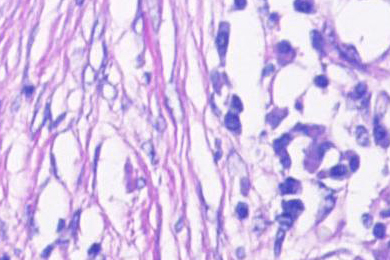

Cytopathology or cytology aims to detect diseases on the cellular level by the study of single cells and cell structures. This pathology discipline was founded in 1928 by the Greek medicine pioneer George Papanicolaou who also invented the “Pap smear”. These smear tests are now commonly used in cytopathology where clinical samples from a wide range of body sites are spread and deposited across a glass microscope slide, resulting in a thin film of cells for subsequent staining and examination by light microscopy.

Prominent examples for exfoliative cytology are the aforementioned Pap smear, where cells are scraped from the cervix with a cervical spatula, or cells that are harvested from bodily fluids such as blood and urine, pleural and pericardial effusion, or ascites from the peritoneum. In intervention or fine-needle aspiration cytology (FNAC) the pathologist uses a small needle to collect cells in various body organs for diagnostic analysis in gynecologic, lymph node, thyroid, breast, liver, lung, kidney or pancreas cytology. These cytological screenings are most commonly used to search for cells going through abnormal changes called hyperplasia and dysplasia that may become cancer cells.

A very good cellular differentiation and clearly visible nuclear details are absolute prerequisites in cytology for carcinoma and tumor cell diagnosis. Cytologists and pathologists rely on crystal-clear images of their samples with the highest color fidelity in brightfield, phase contrast, DIC, or fluorescence. While cytological stains such as Papanicolaou’s (PAP stain), Giemsa, or Romanowski-type result in specific staining of cellular features, it is the optical quality of the microscope, the fidelity of the attached camera for digital documentation, and the ergonomic design of the instrument that can make all the difference when screening patient samples.